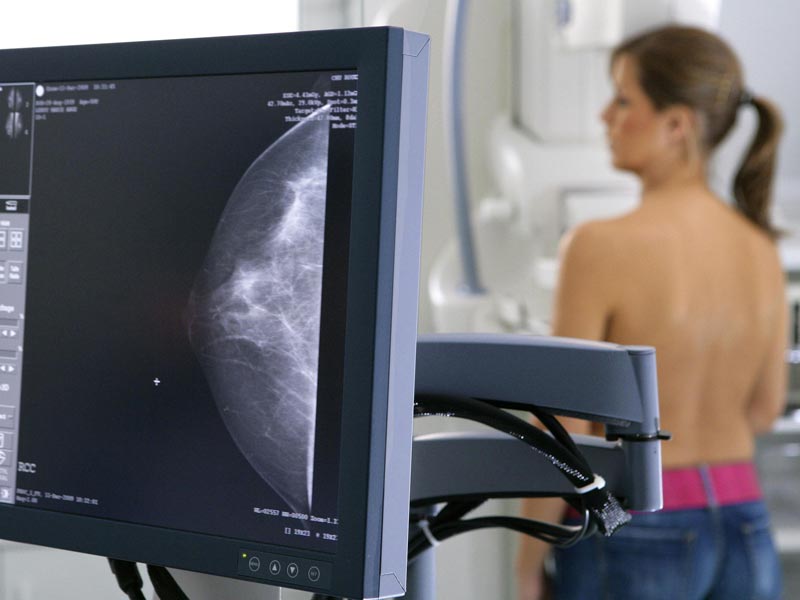

Відразу варто зазначити, що мамографія є абсолютно безболісною та безпечною процедурою. Її проходять, як за розпорядженням лікаря, так і просто з метою діагностики.

До новоутворень відносять також кісти, фіброаденоми, кальцинати, які переважно є доброякісними утвореннями. Кальциноми визначити за пальпації неможливо. Для цього і потрібно робити мамографію. Тому що їхнє розростання може призвести до неприємних наслідків та дискомфорту. Маленьке новоутворення завжди видаляти легше, ніж велике.

Процес мамографії нагадує звичайний рентген чи флюорографію. Мамографію потрібно проводити часто. Вона не впливає на появу чи збільшення новоутворень. Якщо флюорографію можна робити не частіше ніж 2 рази на рік, то з монограмою все простіше. Вона абсолютно нешкідлива.